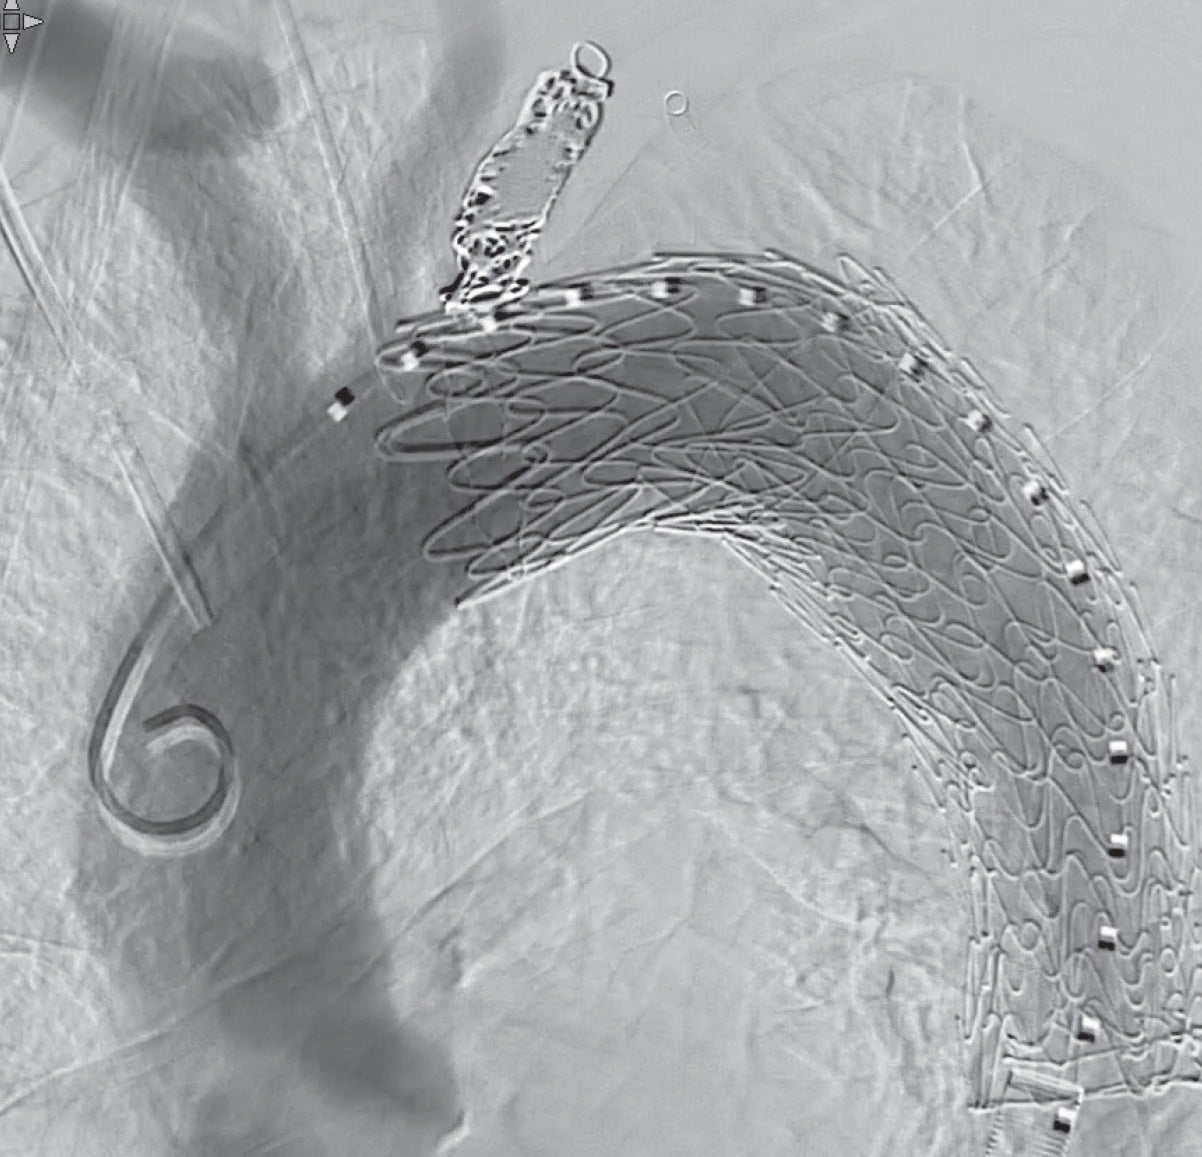

ドライシール フレックス イントロデューサシース内に1本目のTAG® コンフォーマブル ステントグラフト(TGM343410J)を挿入し、ドライシール フレックス イントロデューサシースをEVAR時のように抜退して(図 3b)、大動脈頂部(Zone 3近く)から末梢のランディングゾーンまでステントグラフトでカバーするように静かに展開する。シースとステントグラフトで「 鋪装 」された経路を通して中枢用の2本目のTAG® コンフォーマブル ステントグラフト(TGMR404015J)をZone 2まで先進させ、左鎖骨下動脈バルーンプロテクション下にゆっくり展開して、予定したデバイスを留置した(図5a, b)。

最後に左鎖骨下動脈のバルーンプロテクションを継続したまま、Selecon MP Catheter II内にマイクロカテーテルを挿入し、左鎖骨下動脈の起始部をコイルで塞栓した。